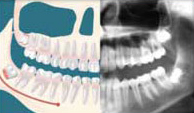

Why Should I Have Them Removed? Although people develop and grow 32 permanent, adult teeth (16 in the upper and 16 in the lower jaw), most do not have enough room in their mouth for all of these teeth to completely erupt. Since the wisdom teeth are the last to develop, they often will not have enough room to adequately erupt into the mouth to become fully functional and cleanable teeth. This lack of room or space can result in a number of harmful effects on your overall dental health. When this occurs they are said to be impacted, indicating their inability to erupt into an alignment that will allow them to be able to function in the chewing process. There are several types of impactions:

Soft Tissue Impactions: There is adequate jawbone to allow the wisdom tooth to erupt but NOT enough room to allow the gum tissue to recede to allow adequate cleaning of the tooth.

Partial Bony Impactions: There is enough space to allow the wisdom tooth to only partially erupt. It cannot function in the chewing process and creates cleaning problems.

Complete Bony Impactions: There is NO space for the tooth to erupt. It remains totally below the jawbone or if even partially visible requires complex removal techniques.

Unusually Difficult Complete Bony Impactions: The impacted Wisdom tooth is in an unusual and difficult to remove position. This situation can also arise when the shape of the jawbone and other facial structures make removal of this tooth significantly more difficult.